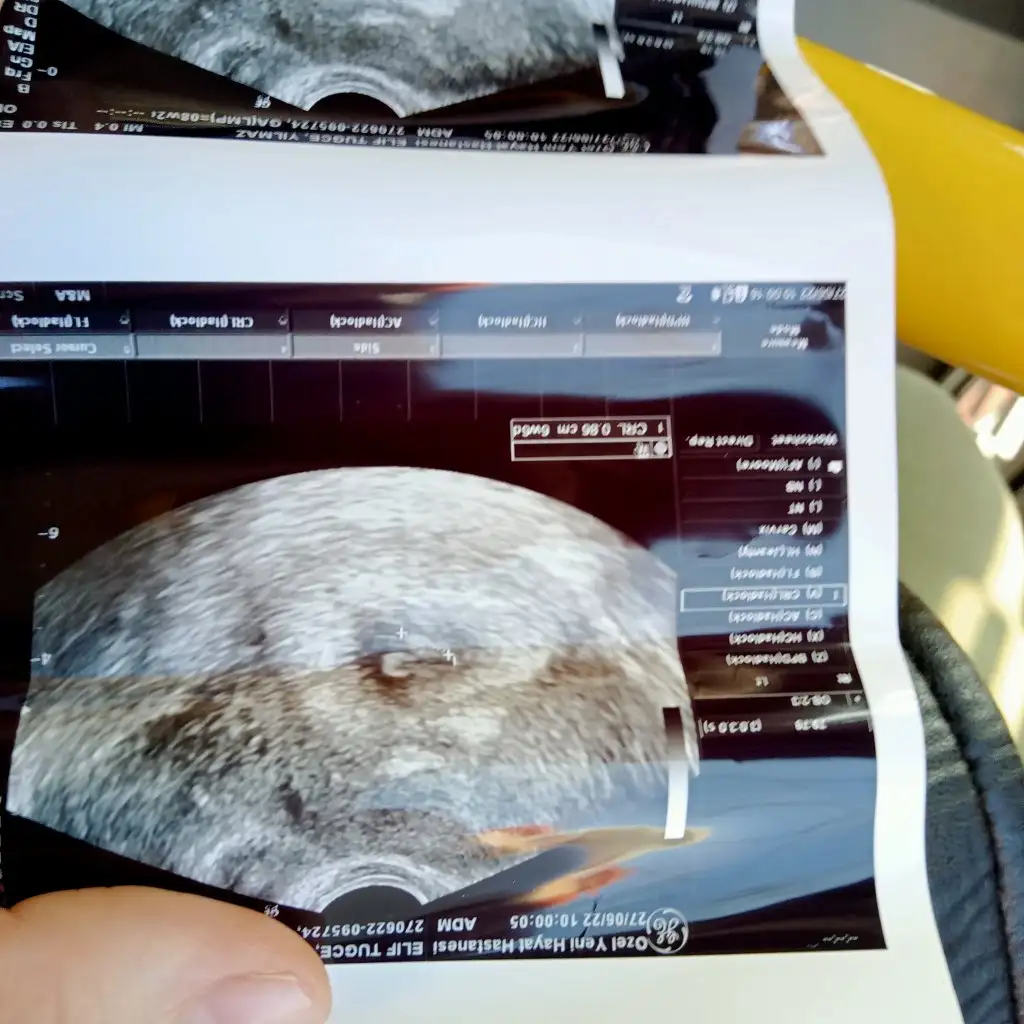

Arkadaşımın bebegi. 11 haftalik karından tahminin nedir acaba canim

IMG-20220622-WA0010.webp